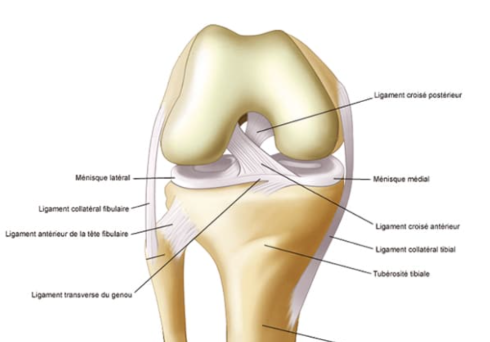

Le ligament croisé antérieur (LCA) est un élément essentiel à la stabilité du genou. Il empêche le tibia de glisser vers l’avant par rapport au fémur. Les blessures du ligament croisé antérieur, fréquentes chez les sportifs pratiquant des activités à fort impact, peuvent provoquer instabilité et perte de performance. Le Dr ALLAOUI Oussama Hamza prend en charge ces lésions avec précision, en combinant expertise chirurgicale et suivi personnalisé pour un retour optimal aux activités.

Le traitement du ligament croisé antérieur dépend de la gravité de la lésion. Dans certains cas, la rééducation et l’utilisation d’orthèses suffisent. Pour les ruptures complètes, une reconstruction chirurgicale est souvent nécessaire. La rééducation post-traitement est essentielle pour retrouver force, mobilité et stabilité. Un programme de prévention, comprenant des exercices ciblés, permet de réduire le risque de récidive et de renforcer l’articulation.